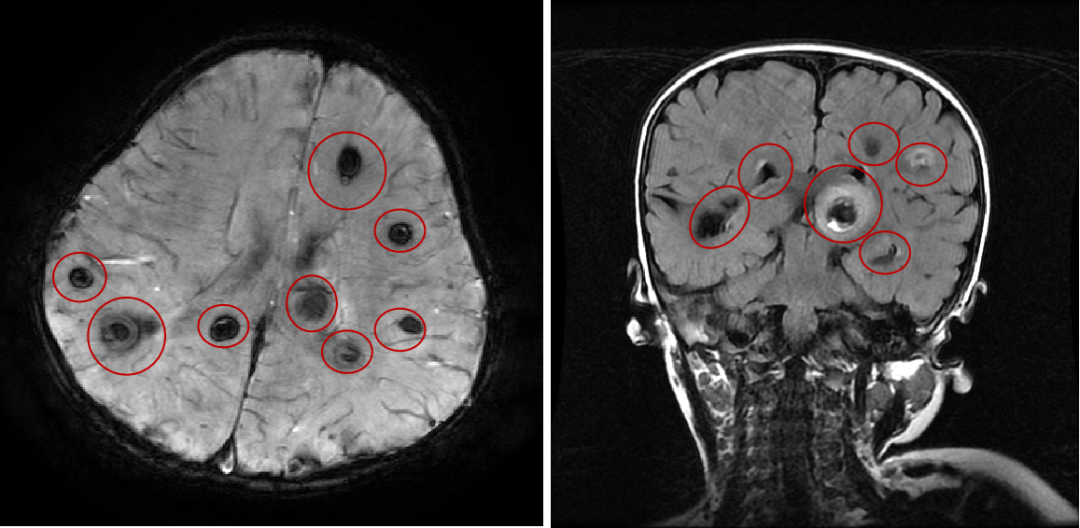

海绵状血管瘤是大脑和脊髓的血管畸形。脑海绵状血管瘤的直径从几毫米到几厘米不等。脑海绵状血管瘤随着时间的推移在大小和数量上增加或减少。根据...

由于脑血管造影不作为海绵状血管瘤患者常规检查,所以脑多发海绵状血管瘤合并颅内动脉瘤发病率不详。海绵状血管畸形常表现为出血﹑癫痫等临床症状...